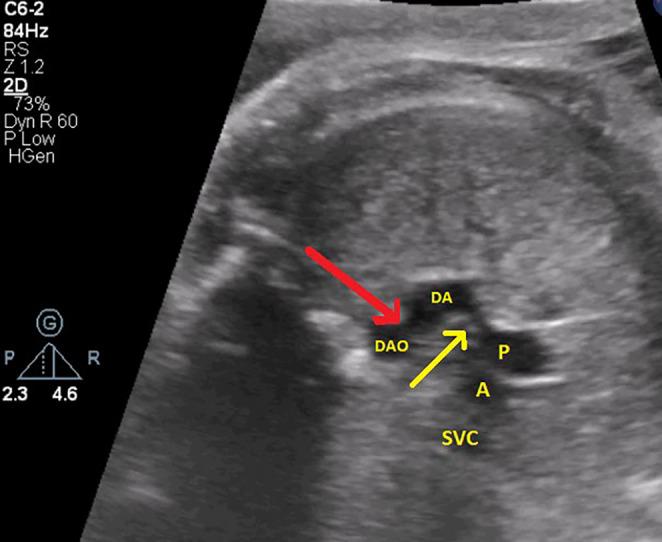

Premature Constriction of Fetal Ductus Arteriosus Caused by Sertraline in a Pregnant Woman: A Case Report.

Fetal ductus arteriosus was treated in a 39-year-old pregnant woman in the 33rd week After psychiatric consultation and discontinuation of sertraline which underscores the association of sertraline with premature ductus arteriosus constriction.

一名39岁的孕妇在孕33周时接受了胎儿动脉导管相关治疗。经过精神科会诊并停用舍曲林治疗,这突出了舍曲林与动脉导管过早收缩之间的关联。